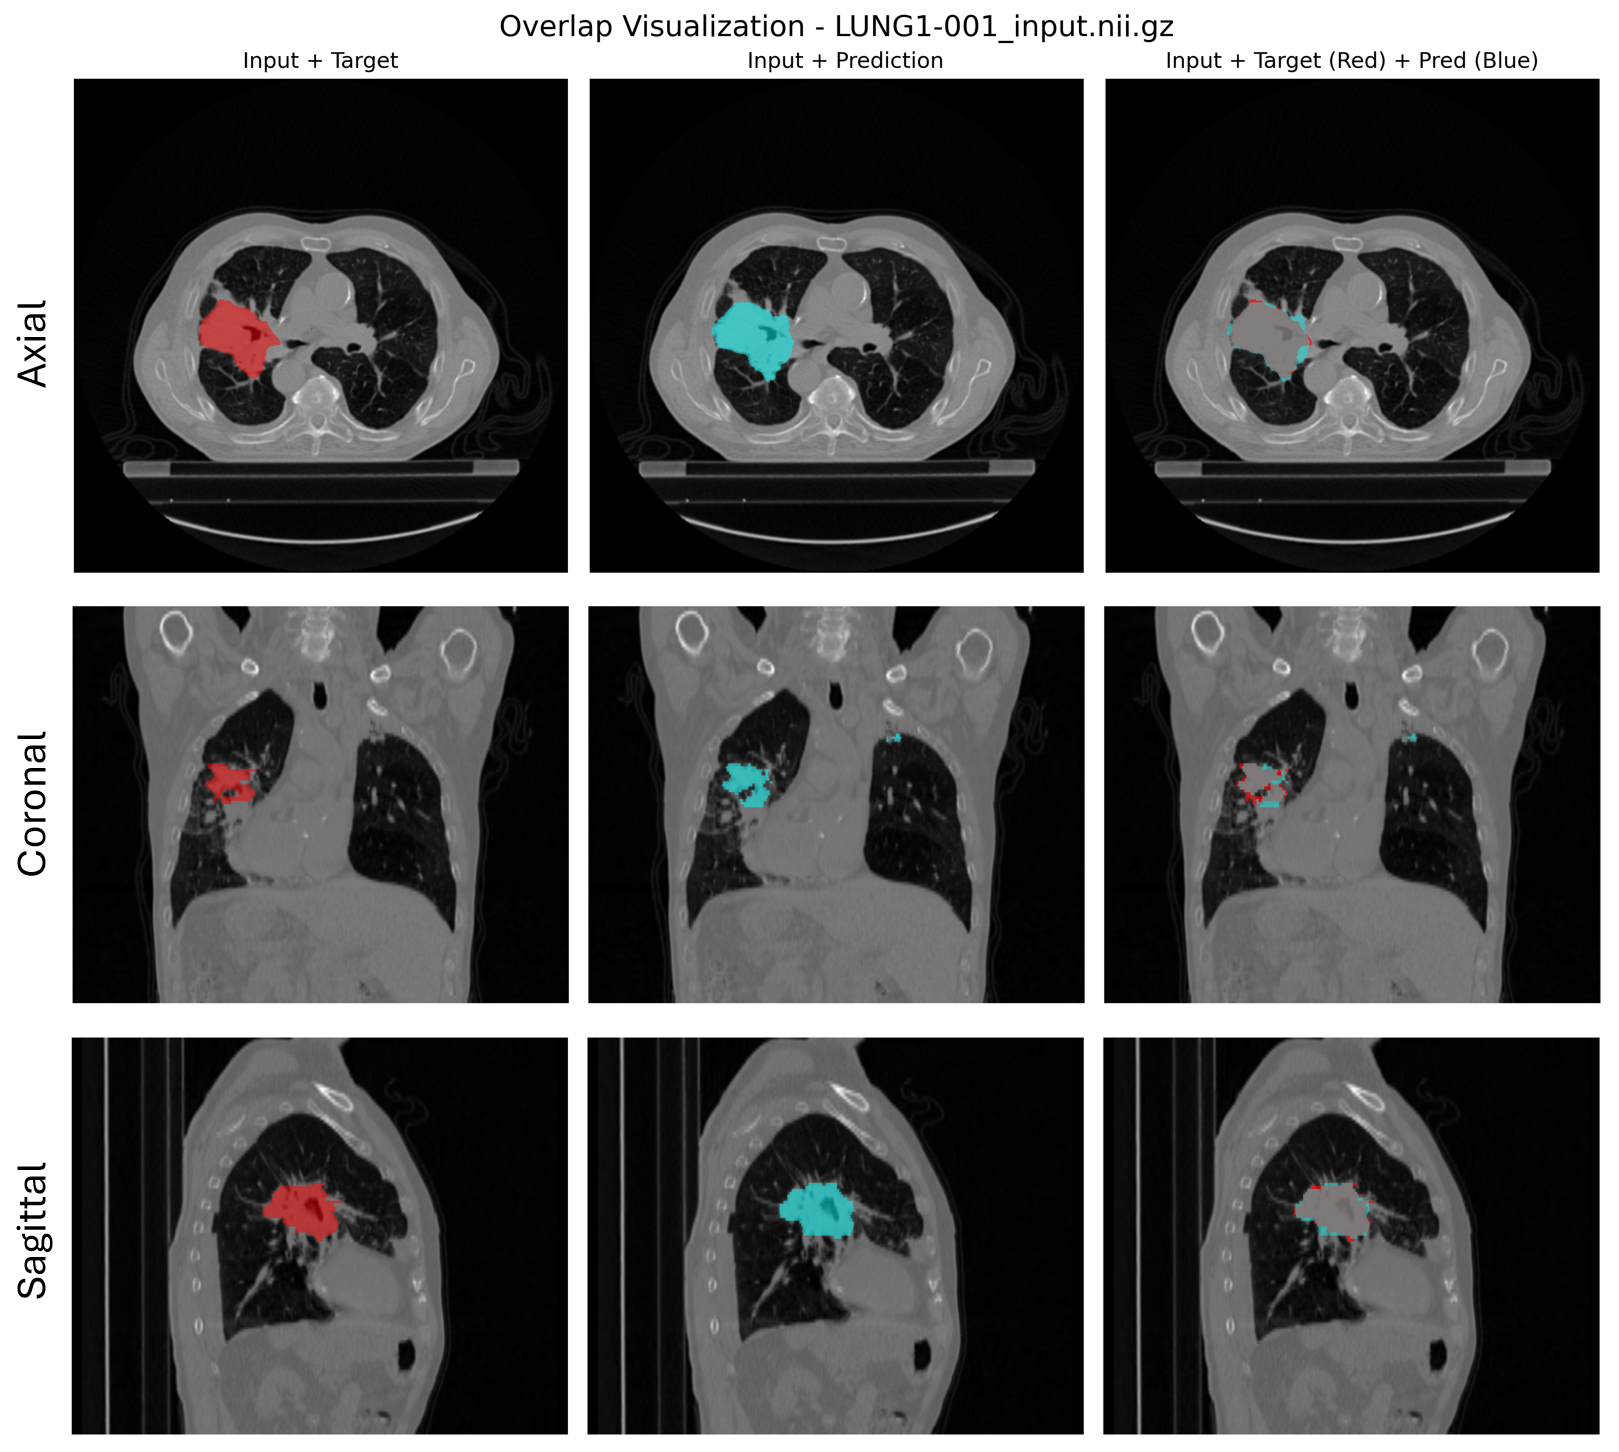

Prediction example:

Figure 3. From left to right: CT scan with the ground truth tumor mask (red), the predicted mask (cyan), and an overlap of both masks to visualize prediction accuracy.#